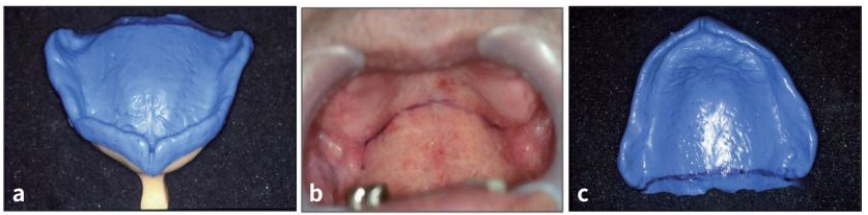

상악 개인용 트레이를 점검하여 트레이의 연장이 적절히 되었는지를 확인한다. 환자의 palate에 indelible pencile을 이용하여 vibrating line을 표시하여 이 선이 hamular notch쪽으로 연장이 되게 하고 트레이의 후방 경계를 이 선에 맞춘다 (그림 22 a, 22 b).

Tuberosity sulcus 부위는 mucosa의 reflection을 확인하기가 어려우므로 의심이 되면 low-fusing compound를 border에 조금 첨가하여 확인하며 트레이의 border가 과연장된 경우 denture bur 등을 이용하여 삭제하고 저연장된 경우는 low-fusing compound를 첨가하여 보충할 수 있다. 그리고 입술과 뺨을 들어 올려 트레이에 border가 sulcus reflection보다 조금 짧은지를 점검한다(그림 22 c).